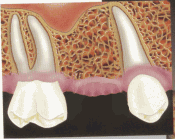

Now, with dental implants, we can restore your missing teeth without needing to grind down adjacent teeth (crown & bridge) or employ traditional dentures (ridge supported and retained).